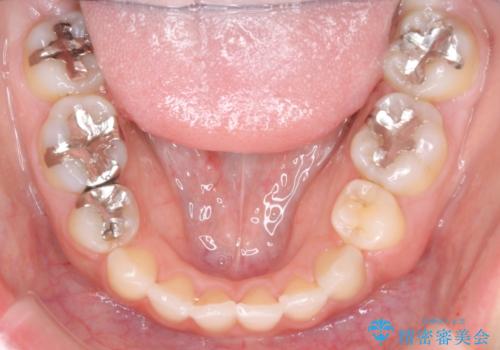

- 口元が出てるのが気になるとのことで来院されました。

上下左右前から4番目の歯を抜歯して前歯を後方に下げて、口元を下げる計画としました。

口元を大きく改善したい場合は抜歯が必要となることが多いです。